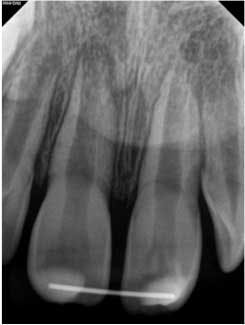

At approximately one year, the patient returned for follow-up. Clinical testing was equivalent to earlier recall visits. Radiographically, the tooth showed continued apical development with further development of a calcific barrier at the fracture line (figure 4). Furthermore, the medial aspect of the fractures showed repair.